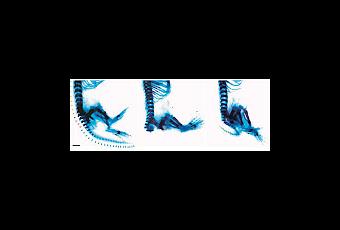

Los científicos generaron células madre y en modelos de ratón recrearon el síndrome de Zaki y trataron la afección con el medicamento CHIR99021, que aumenta la señalización de Wnt. En cada modelo de ratón , encontraron que CHIR99021 impulsó las señales de Wnt y restableció el desarrollo. Los embriones de ratón desarrollaron partes del cuerpo que habían faltado y los órganos reanudaron el crecimiento normal. Este medicamento, o medicamentos similares, eventualmente se usarán para prevenir defectos de nacimiento, si los fetos pueden ser diagnosticados lo suficientemente temprano.